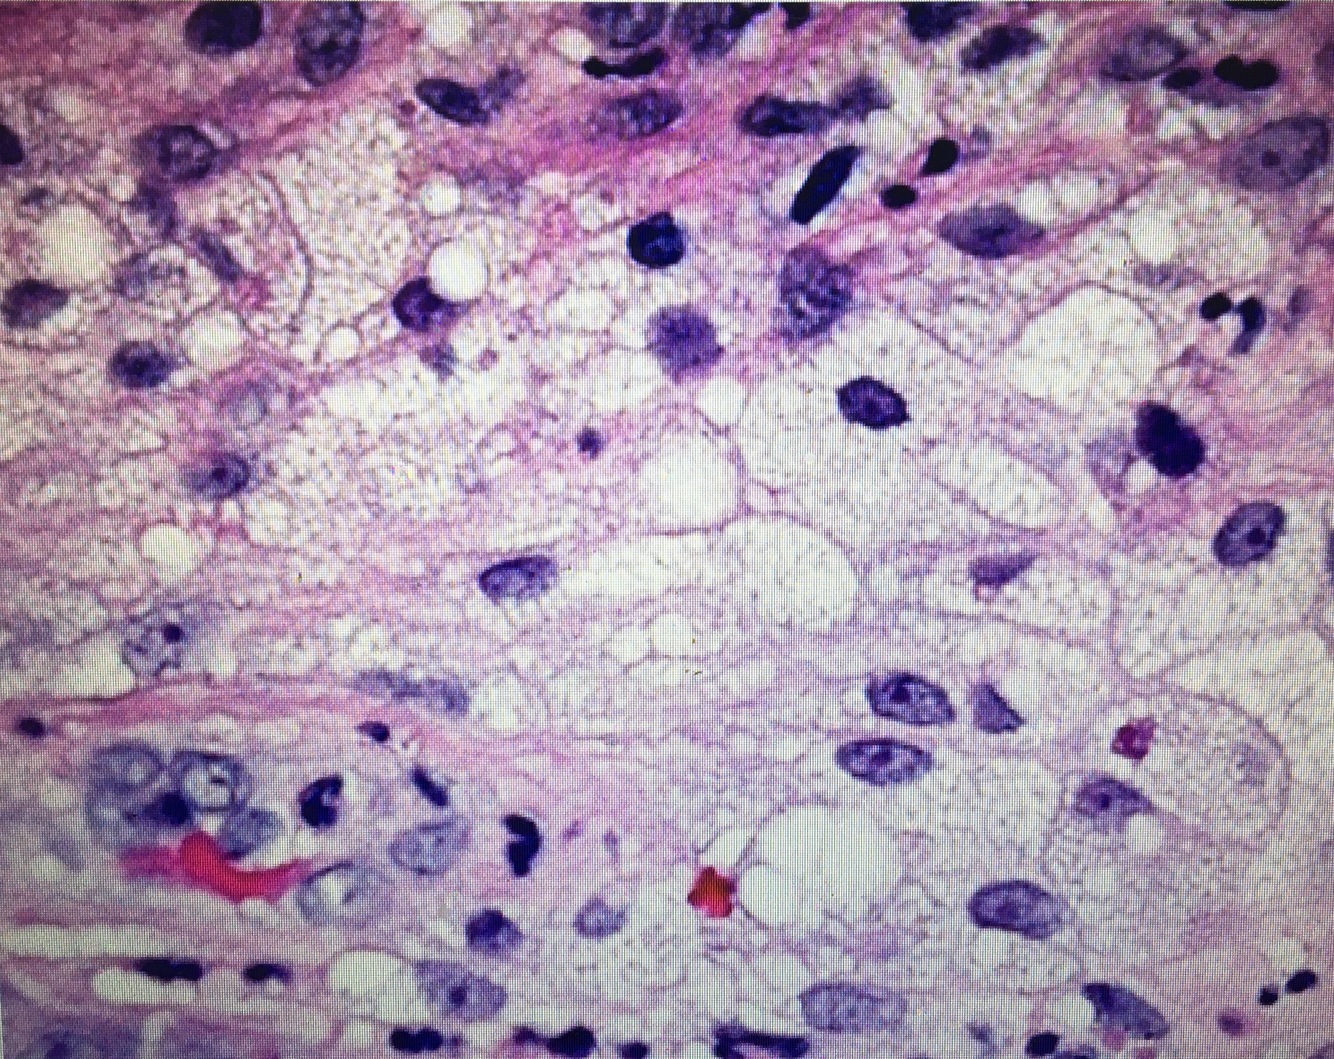

This microscopy taken from upper eyelid indicates what?

Xanthelasma (Lipid Laden Macrophages–> Foam cells) seen in Hyperlipidemia